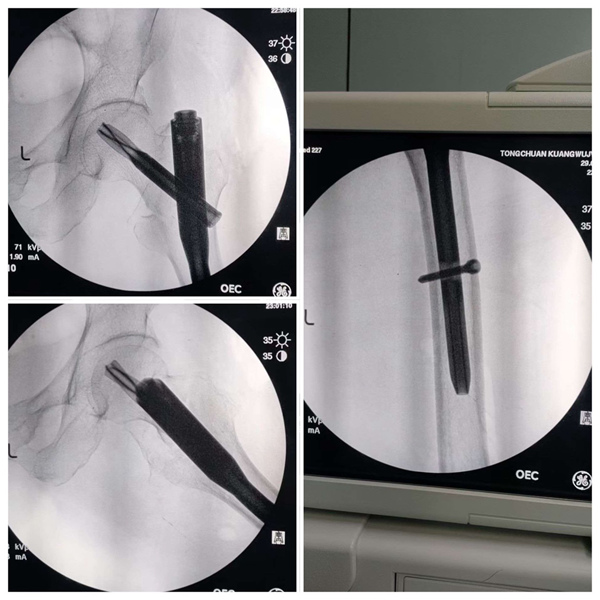

万事俱备,东风徐来。骨二科手术团队在副院长贾玉龙、主任杨坤带领团队在手麻科的配合下,为戴老太太行粗隆间骨折微创手术,3个切口共5cm,历时20分钟,手术顺利完成。

目前患者已安返病房,神志清楚,恢复良好,住院医师景喜民、护士长陈凯带领护士们完成查房,进行了床头交接。